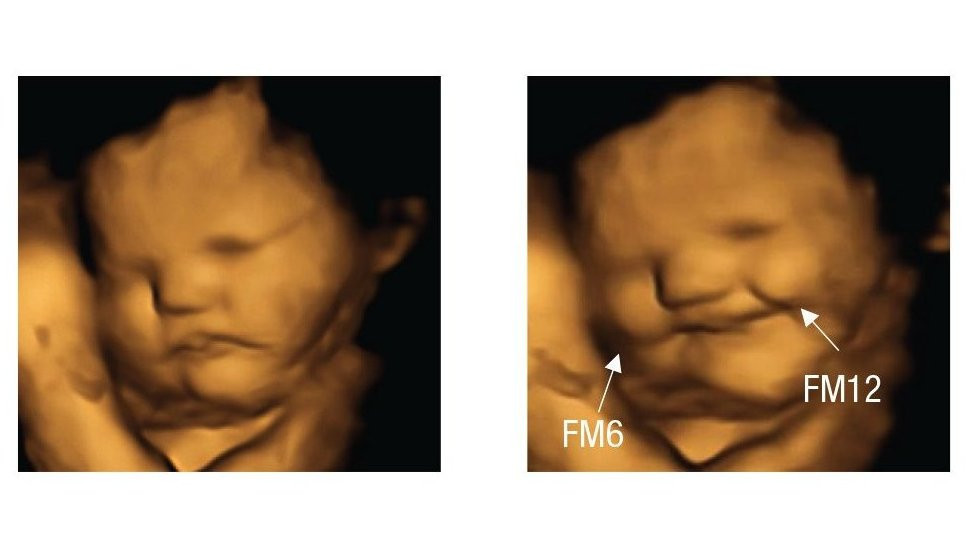

Fetal and Neonatal Research Lab, Durham UniversityReakcije ovog fetusa koji izgleda kao da se smeje, fotografisane su 20 minuta nakon što su majke konzumirale kapsule šargarepe u prahu Ukoliko vas ukus kelja tera da napravite grimasu, niste jedini. Naučnici su otkrili da se fetusi u materici smeškaju kada majke pojedu šargarepu i izgledaju kao da […]

U časopisu Psihološka nauka istraživači su objavili da su 20 minuta nakon što su majke progutale kapsule, 4D ultrazvučni pregledi pokazali da većina fetusa izloženih kelju izgleda kao da pravi grimasu.

U međuvremenu, oni koji su osetili ukus šargarepe su se smeškali.

Grimase i osmesi koji se vide na ultrazvuku „možda su samo pokreti mišića koji reaguju na gorak ukus“, kaže Rajsland.